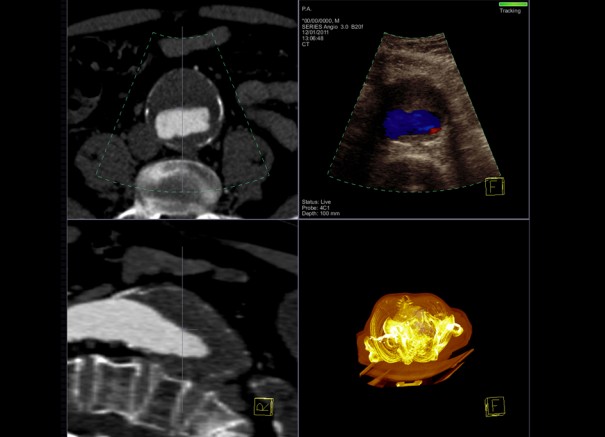

The company Siemens has created the Acuson S3000 device with which computed tomography or magnetic resonance imaging is fused, with ultrasounds using the scanner map as a pattern to know where the lesion is and thus make the puncture through echo.

Often, with a primary technique such as CT or MRI, it is difficult to diagnose an injury or pathology accurately. However, by adding images of different techniques, a higher quality image is obtained and, therefore, a much more reliable diagnosis. In addition to facilitating a more accurate decision about the injury or pathology, image fusion, has significant advantages in terms of security, comfort and cost savings when performing a biopsy. When CT images are fused with ultrasound, the scanner map is used as a pattern to know where the lesion is and thus make the puncture through echo. In this way, avoid exposing the patient again to radiation and reduce waiting lists and high costs of tests such as CT or MAGNETIC Resonance Imaging.

nevertheless, current fusion techniques require manual recording of CT or MRI images, a process that is slow. The patient is also required to lie down and immobile throughout the scan to avoid manual realignments.. To overcome these limitations, Siemens Healthcare has launched its latest platform for ultrasound, the Acuson S3000. This new ultrasound system represents an important advance for this field, in which Siemens is a pioneer with its patented eSie Fusion technology. This system allows automatic fusion of computerized tomographic images (TC) in 3D with real-time ultrasound with a single click. In this way, the registration of the CT image is reduced to a few seconds and the manual registration techniques are significantly simplified, thus optimizing the workflow during the volume registration in the MRI.